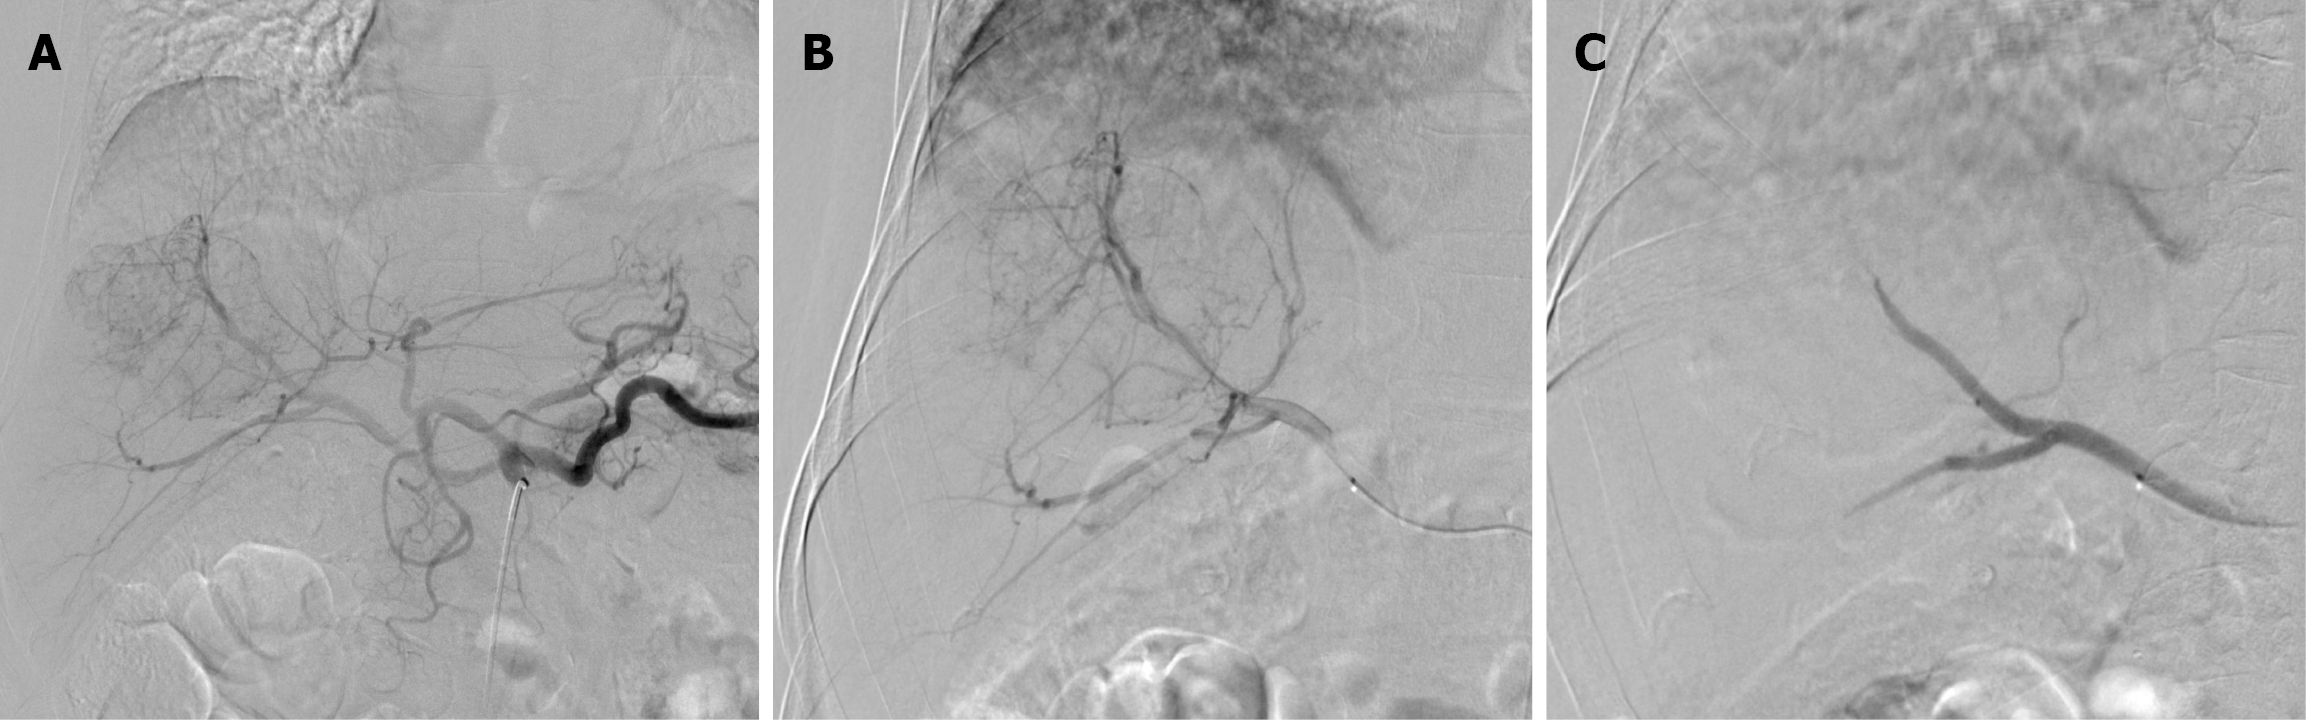

Figure 3 Digital subtraction angiography images during the first drug-eluting bead transarterial chemoembolization session in Case 1.

A: Right hepatic artery non-selective angiogram; B: Selective hepatic angiogram showed a hypervascular mass; C: Superselective angiogram demonstrated complete stasis of the vascular supply of the tumor after embolization.